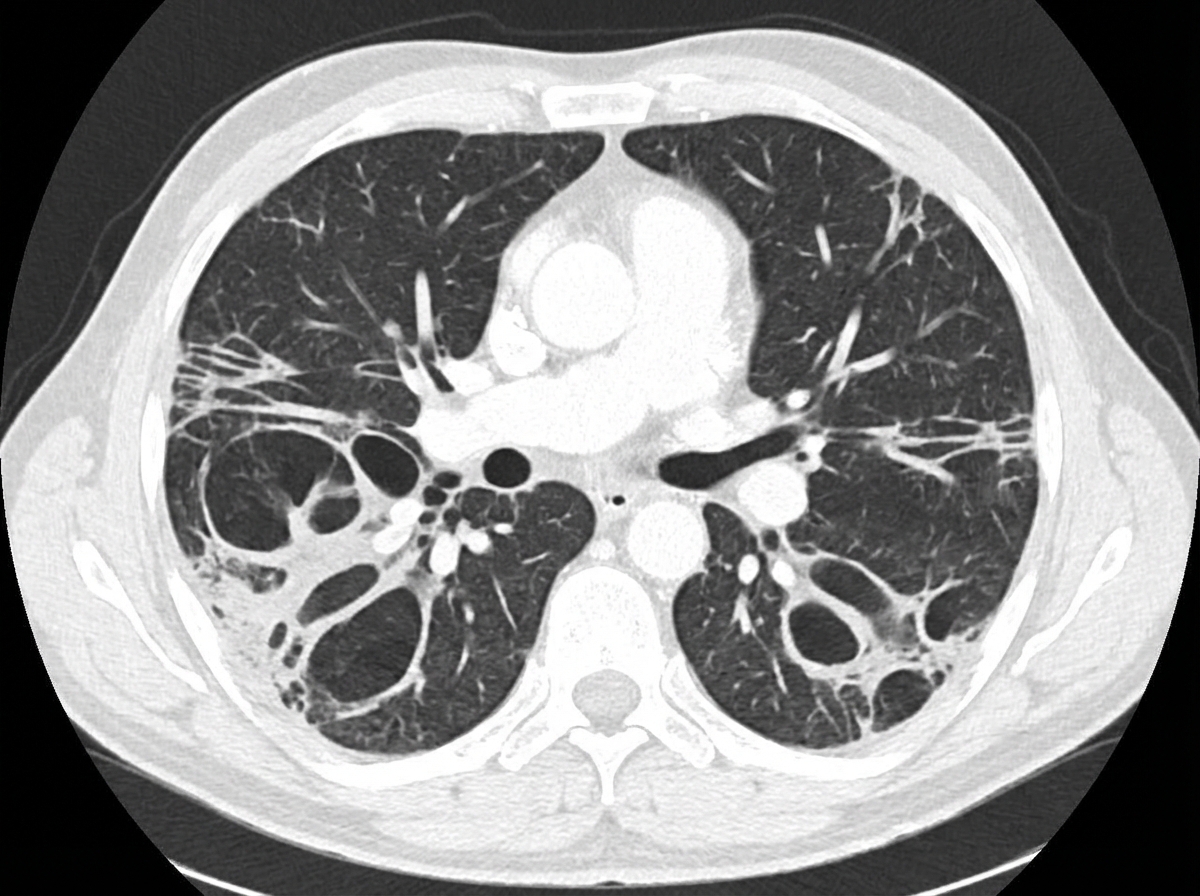

A 55-year-old non-smoker lady presented with on and off haemoptysis and productive cough for 1 year. There was no fever or constitutional symptoms. Physical examination showed clubbing of fingers and coarse crepitations over the lung base. Blood tests were essentially normal and an initial CXR and CT scan were performed. What is the radiological diagnosis?

Explanation: ***Bronchiectasis*** - **Chronic productive cough** with **haemoptysis** and **clubbing** are classic features of bronchiectasis, supported by **coarse crepitations** at lung bases. - CT shows characteristic **signet-ring sign** and **tram-tracking** (dilated airways with thickened walls), while CXR may show **dilated bronchi** and **increased lung markings**. *Pneumoconiosis* - Requires **occupational exposure** to dust particles (silica, asbestos, coal), which is not mentioned in this case. - Typically presents with **progressive dyspnea** and **upper lobe involvement** on imaging, not the described clinical features. *Emphysema* - Strongly associated with **smoking history**, which is absent in this non-smoker patient. - Characterized by **hyperinflated lungs** and **reduced lung markings** on imaging, opposite to the coarse crepitations found here. *Lung abscess* - Usually presents with **fever**, **constitutional symptoms**, and **purulent sputum**, all of which are absent. - CT typically shows a **cavitary lesion** with **air-fluid level**, not the diffuse changes expected in this case.